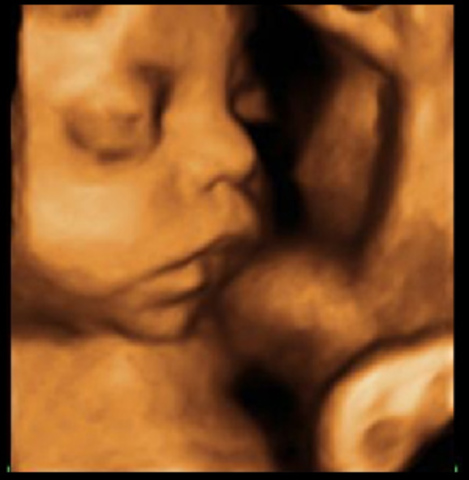

Ahora tiene cejas delgadas, cabello en la cabellera y miembros muy bien desarrollados. La forma y las proporciones generales del bebé son completamente humanas, ya oye, ve luz ,se mueve, traga, orina, quizás comienza a tener memoria, etc.

• Semana 21

Semana 21